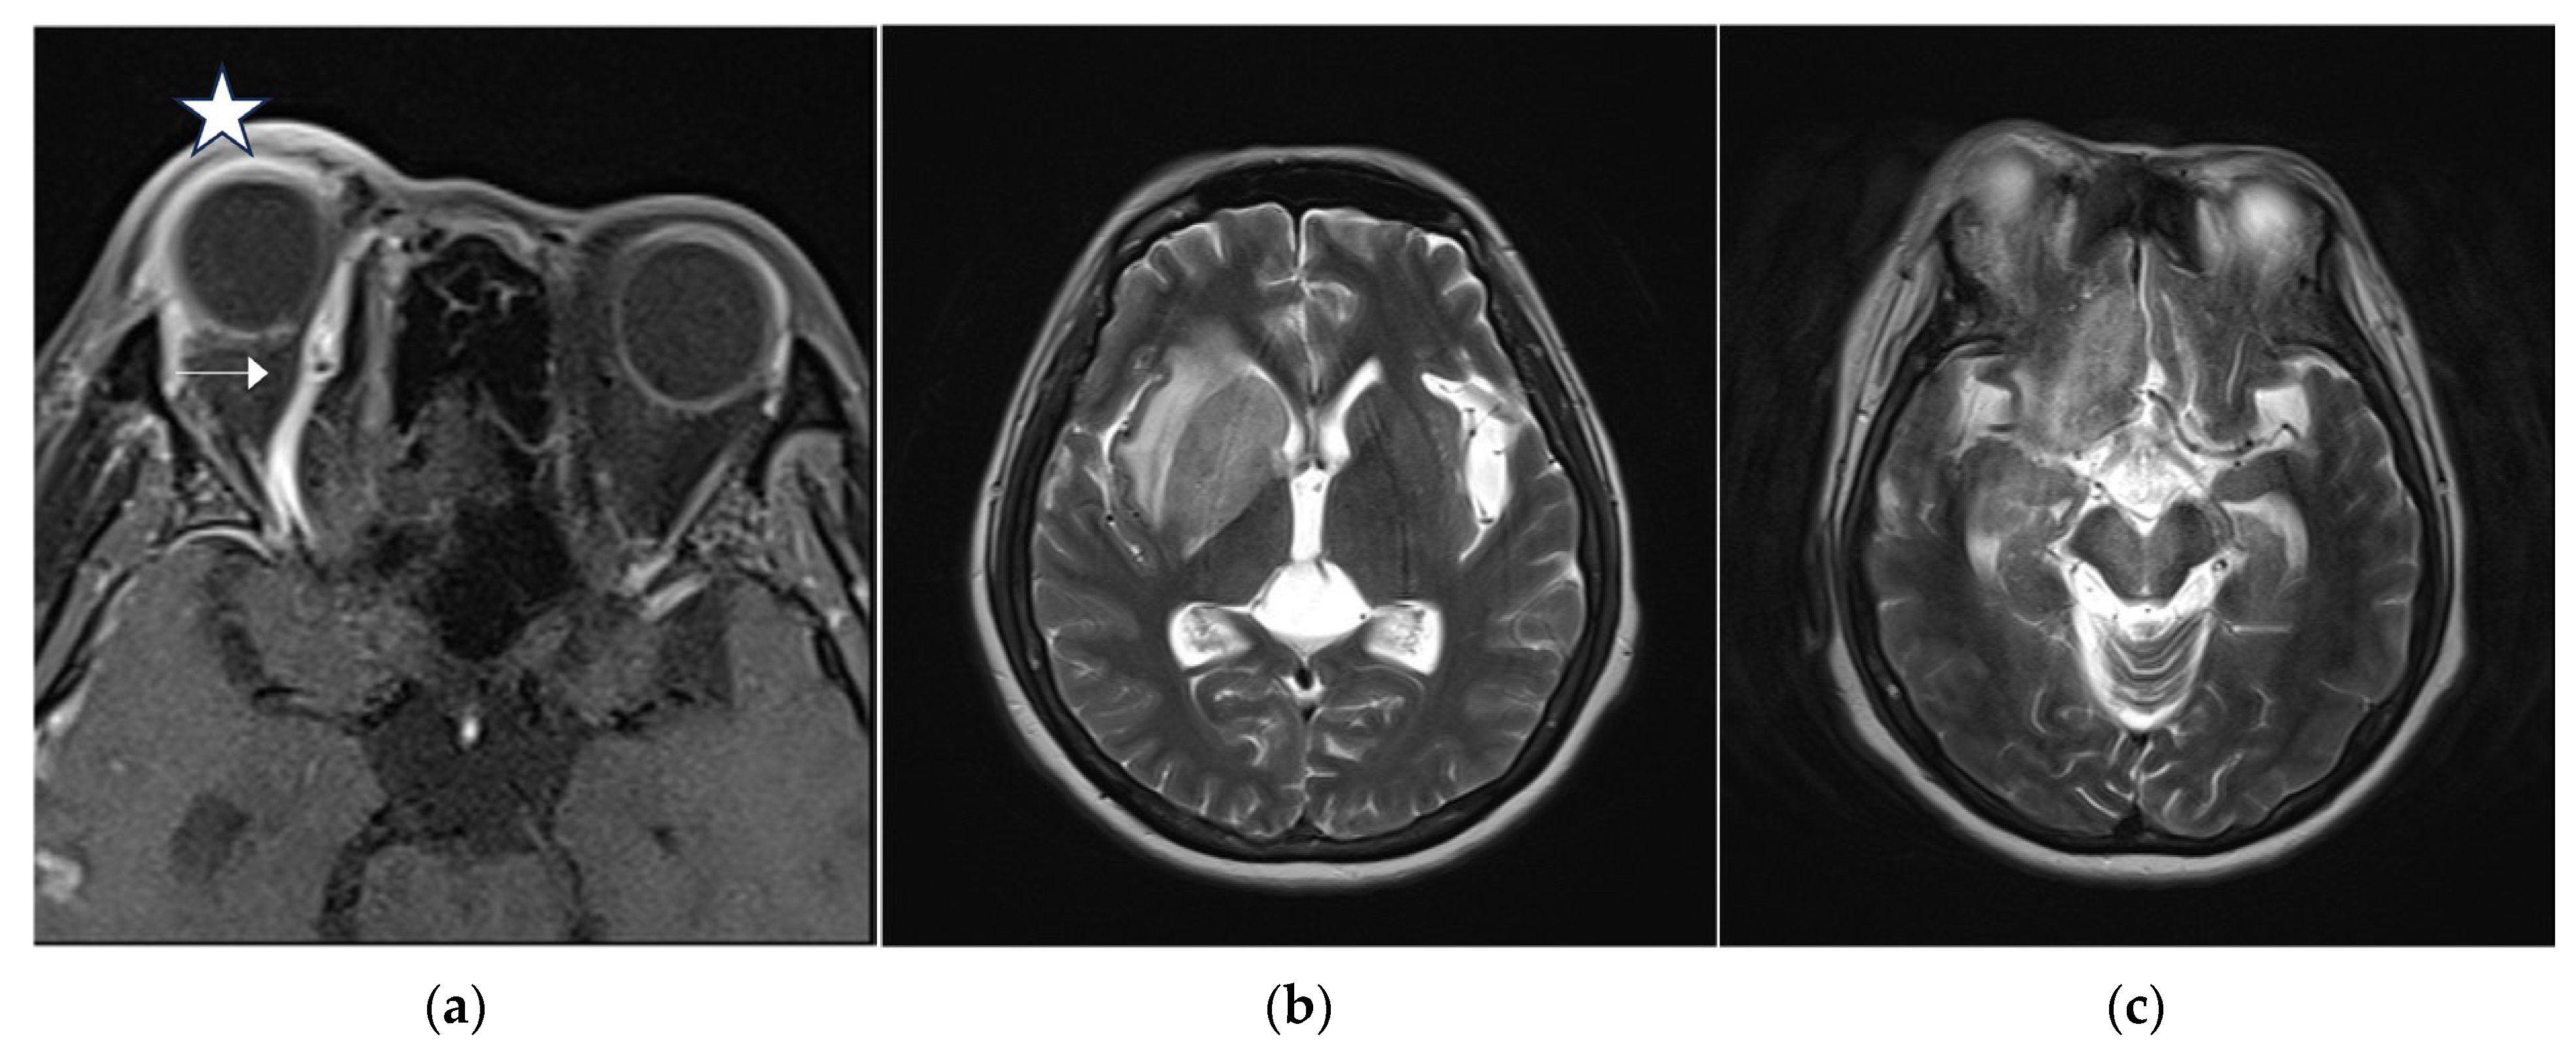

A 46-year-old woman with medically controlled hyperthyroidism was a victim of a motor vehicle accident on the road. The accident led to poor consciousness with Glasgow Coma Scale (GCS) level at E4V1M4, nasal bleeding, and left otorrhea in the patient. A brain computed tomography (CT) scan (Figure 1) showed a small subdural hematoma over the right temporal lobe, right Sylvian subarachnoid hemorrhage, and a right sellar floor fracture with sphenoid sinus hematoma upon arrival at the emergency room. The patient underwent right intracranial pressure monitor insertion for further monitoring and intensive care. Fortunately, the severity of traumatic brain injury did not progress. She gradually regained consciousness 3 days post-trauma. However, she complained of a progressive right eye floater and flash 4 weeks later, so she visited an ophthalmologist for further evaluation. Initial examination revealed right eye proptosis and conjunctival vessels engorgement, without chemosis, or tinnitus in the right ear. (Figure 2a) Rapidly progressive severe right eye exophthalmos, audible bruits, and chemosis (Figure 2b) developed within several days, highly suggesting right carotid cavernous fistula. The visual acuity and intraocular pressure data before treatment and one month post-treatment of the CCF are listed in Table 1. In addition, she became unconscious (GCS E3V2M5) and had left limb hemiplegia. A brain magnetic resonance imaging (MRI) (Figure 3a) disclosed engorgement of the right SOV and swelling of right orbital cavity (the MRI protocol we used is listed below in Table 2). In addition, high T2-weighted imaging signal changes were observed in the right corpus striatum (Figure 3b), right insular lobe, right inferior frontal lobe, right medial temporal lobe, midbrain, and pons (Figure 3c), which indicate perifocal brain edema.

Figure 3.

(a) Brain magnetic resonance imaging (MRI) axial view, T1-weighted imaging with contrast disclosed engorgement of right superior ophthalmic vein (arrow head), and swelling of right orbital cavity (star); (b) brain MRI axial view, T2-weighted imaging show high T2 signal change in right corpus striatum; and (c) axial view of brain MRI T2-weighted imaging show enhancement at right insular lobe, right frontal inferior lobe, right medial temporal lobe, midbrain, and pons, which indicate perifocal cerebral edema.